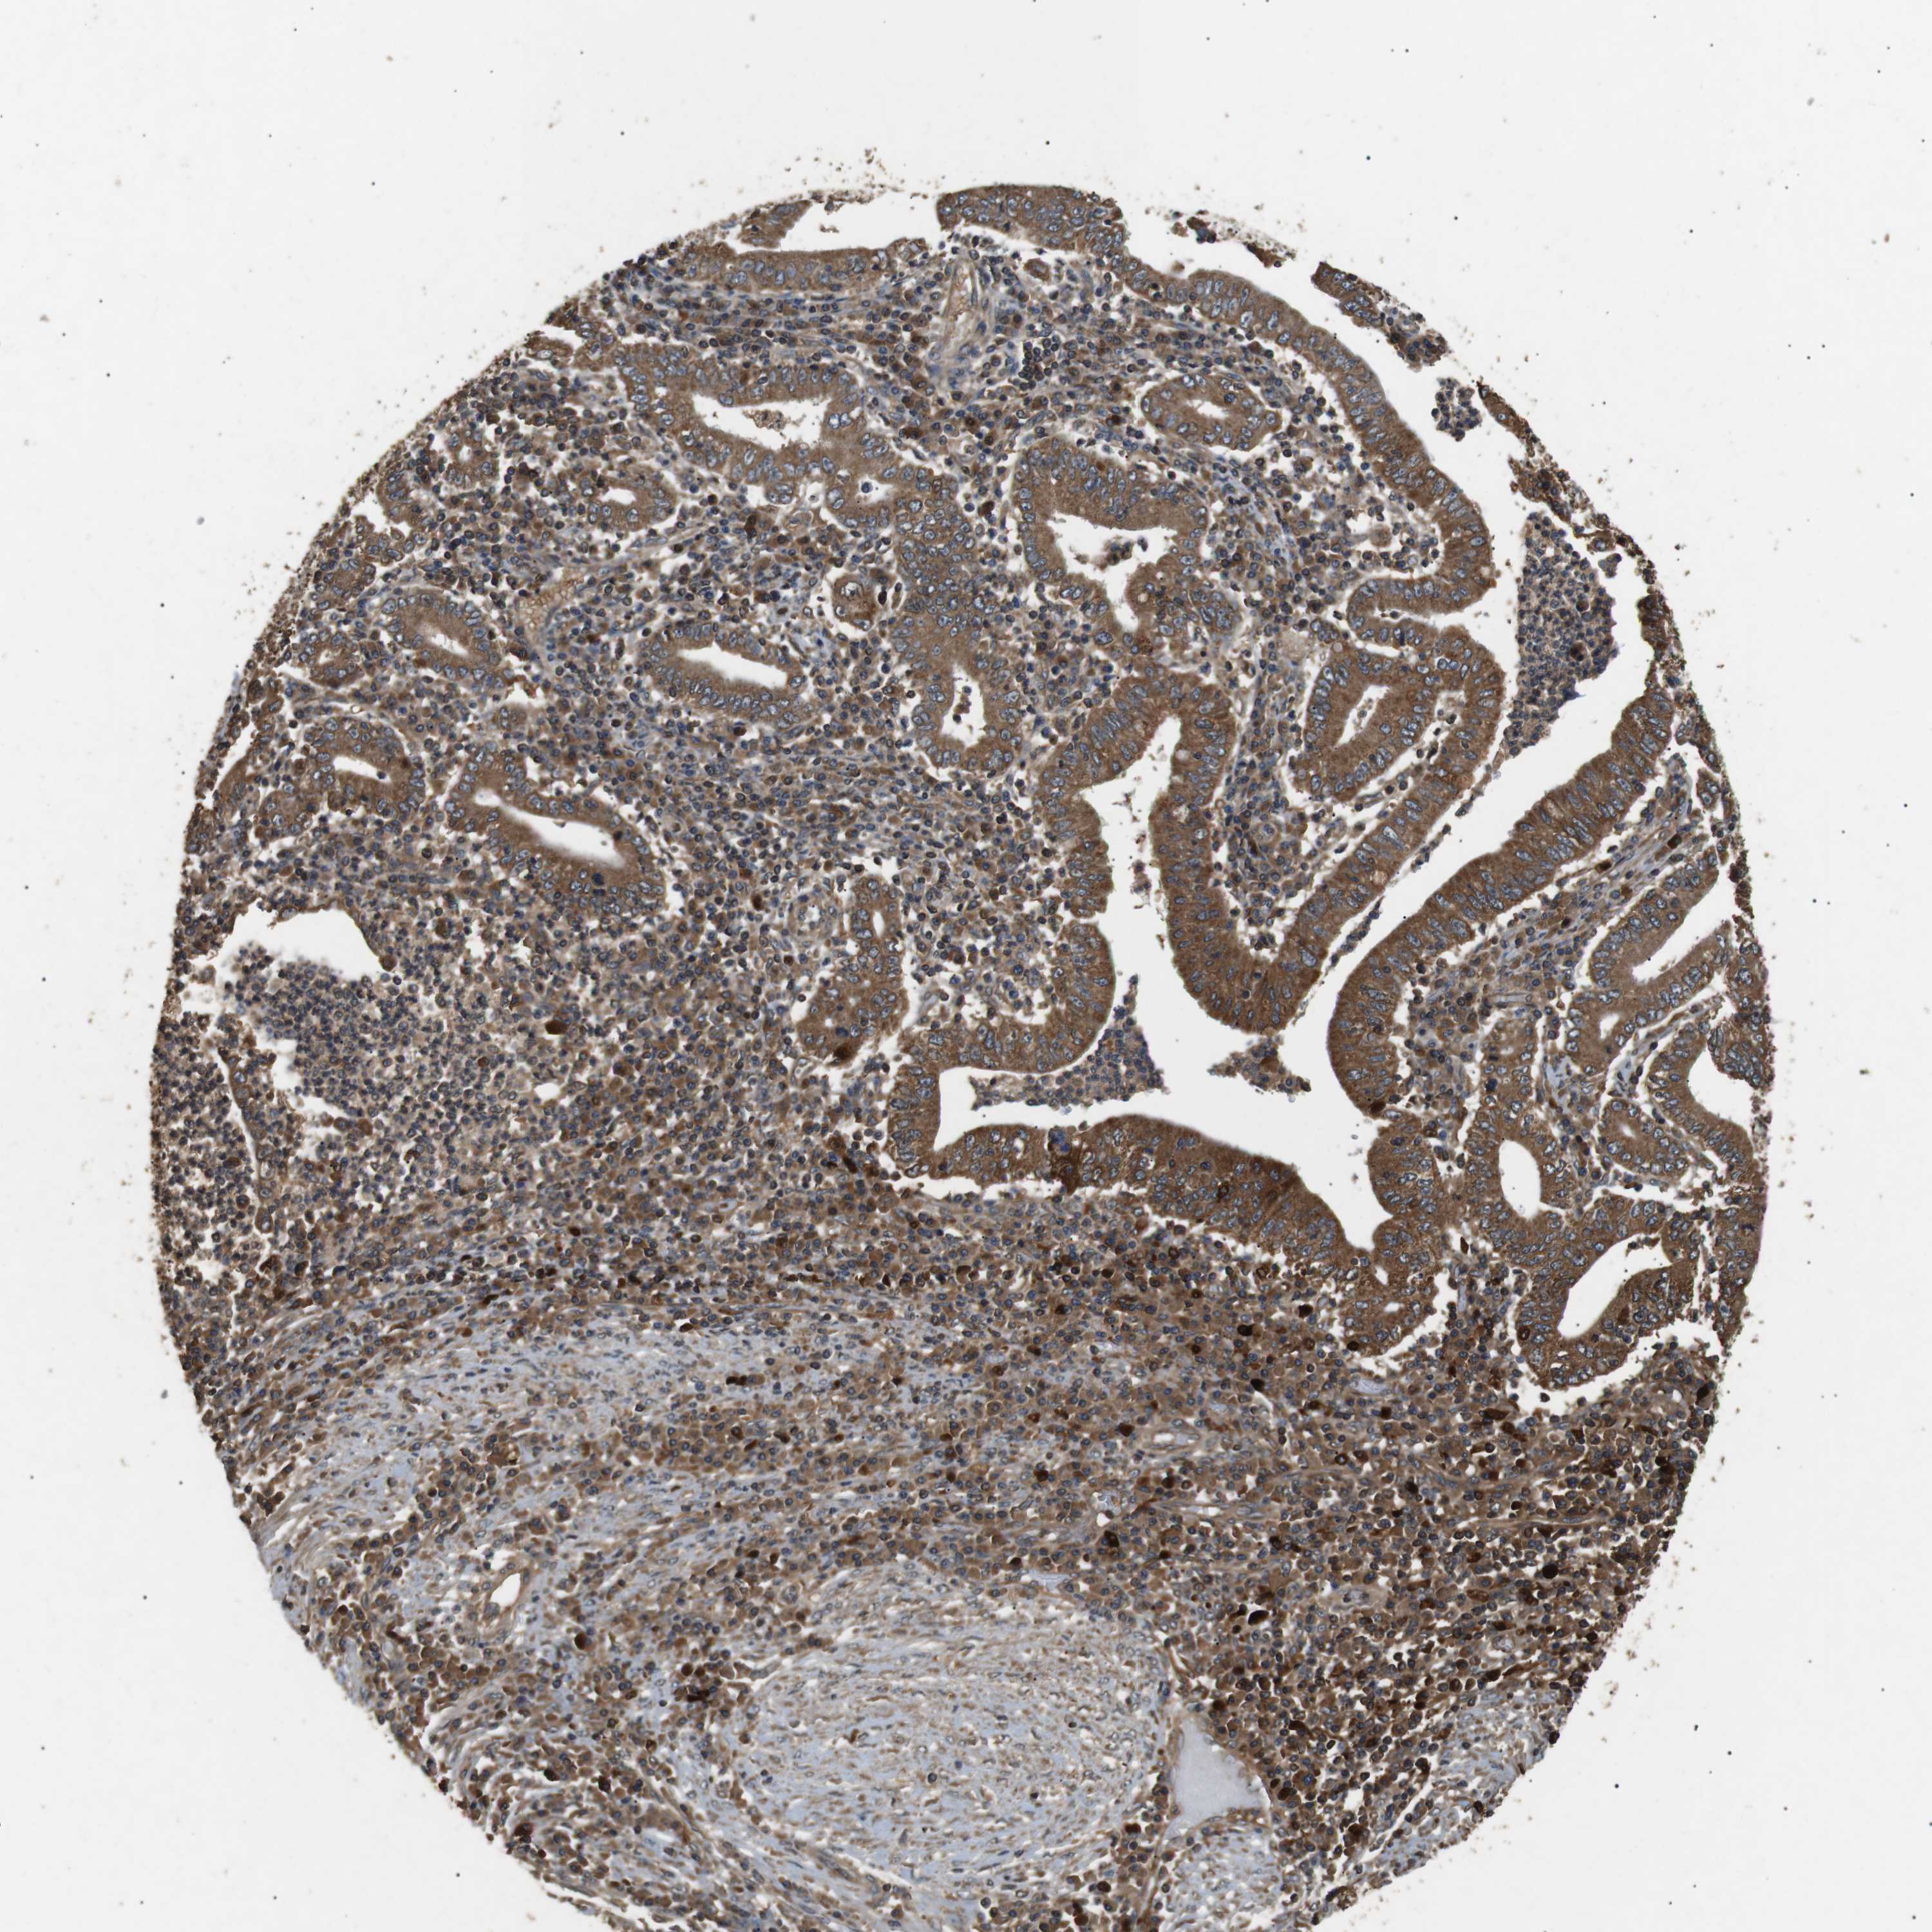

STOMACH CANCER - Protein expressioni

A mouse-over function shows sample information and annotation data. Click on an image to view it in a full screen mode. Samples can be filtered based on level of antibody staining by selecting one or several of the following categories: high, medium, low and not detected. The assay and annotation is described here.

Note that samples used for immunohistochemistry by the Human Protein Atlas do not correspond to samples in the TCGA dataset.

Antibody stainingi

Antibody staining in the annotated cell types in the current human tissue is reported as not detected, low, medium, or high, based on conventional immunohistochemistry profiling in selected tissues. This score is based on the combination of the staining intensity and fraction of stained cells.

Each image is clickable and will lead to virtual microscopy that enables deeper exploration of all samples and also displays staining intensity scores, fraction scores and subcellular localization as well as patient and tissue information for each sample.

Antibody HPA013388

Antibody HPA015592

Staining

High

Medium

Low

Not detected

Intensity

Strong

Moderate

Weak

Negative

Quantity

>75%

75%-25%

<25%

None

Location

Nuclear

Cytoplasmic/membranous

Cytoplasmic/membranous,nuclear

Adenocarcinoma, NOS